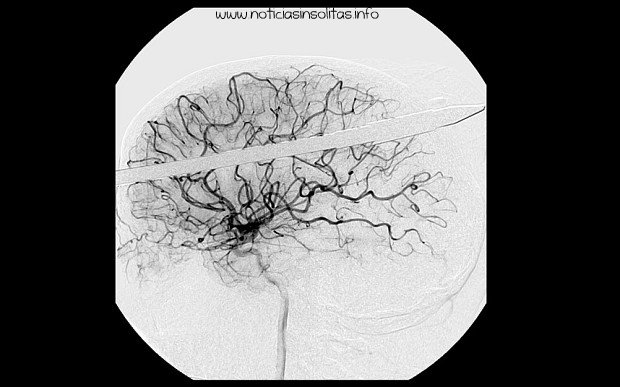

Yasser López, de 16 años, puede sentirse muy afortunado de haber sobrevivido tras el accidente ocurrido en un lago de Florida donde se encontraba pescando con un amigo. El amigo que le acompañaba se le disparó por error un arpón de pesca y este impactó sobre la cabeza de López. López enseguida perdió la consciencia y fue trasladado en helicóptero al Jackson Memorial Hospital de Miami, donde los médicos tuvieron que serrar parte de la lanza para que pudiera caber en el escáner. Milagrosamente, la lanza se dirigió directamente a través de su cerebro, pasando muy cerca de su ojo derecho y perforando la parte derecha de su cerebro. El neurocirujano Ross Bullock, afirma que López tuvo mucha suerte, ya que la lanza no llegó afectar los vasos sanguíneos del cerebro.

La radiografía reveló que la punta de la lanza era de tornillo, buscaron la manera de desenroscar la lanza sin tener que arrastrarla a través de su cerebro, y finalmente tras tres horas de operación lograron retirarla sin causar más daños al paciente. Ahora López sufre amnesia post-traumática y no recuerda nada de lo que ocurrió aquel día, y también tiene problemas para mover el lado izquierdo de su cuerpo, aunque los médicos creen que podrá recuperarse completamente.